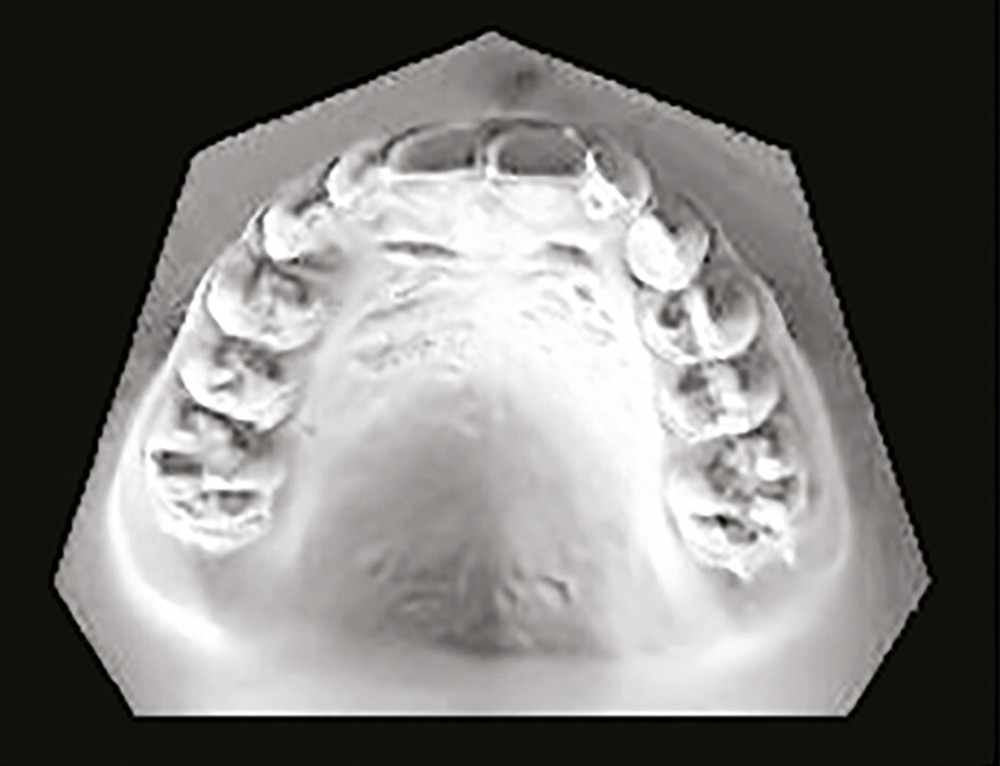

Son profil convexe s’inscrit dans un contexte de classe II squelettique par rétrognathie mandibulaire normodivergente sur un schéma de Classe II/2 avec supraclusion et encombrement modéré (fig. 1 à 7).

La formule dentaire est complète, avec un léger retard d’évolution des deuxièmes molaires (fig. 8).